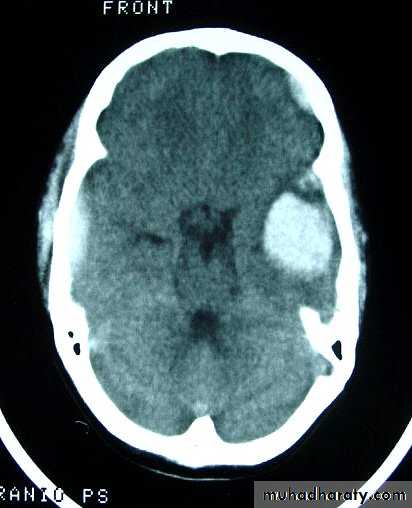

b. Subdural Haematoma

They are the most common intracranial mass lesions resulting from head trauma.

They are classified depending on how long they take to present clinically following the injury into:

Acute Subdural Haematoma: less than 3 days

Subacute Subdural Haematoma: 4-21 days

Chronic Subdural Haematoma more than 21 days.

Acute Subdural Haematoma

Usually due to MORE SEVER high velocity trauma and thus associated with a poorer outcome.

Source of bleeding (haematoma): include:

Most result from torn bridging veins or focal tears of a cortical artery.

Cortical lacerations or contusions.

Bleeding from tears in the dural venous sinuses.

Clinical Picture: patient will present with a picture similar to that of an extradural haematoma, but there is persistent loss of consciousness with no lucid interval.

Ct scan will show a concave hyperdence collection because blood follows the subdural space over the convexity of the brain.

Acute Subdural Haematoma are rapidly evolving lesions and early evacuation via craniotomy is mandatory.